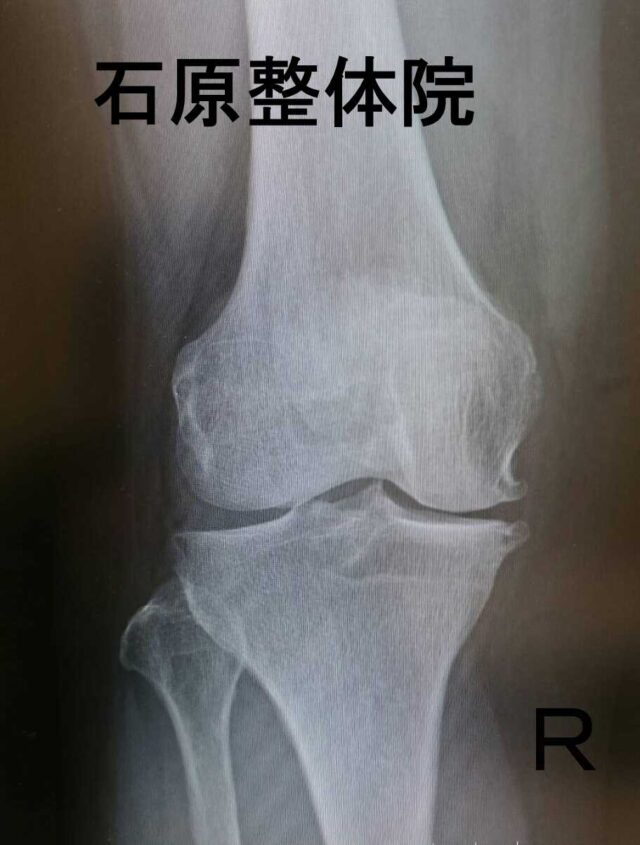

【膝に水が溜まる】階段の上り下りが痛みなくできるようになり、痛みの恐怖心が取れました!

Q.当院に来院される前、どのような症状で悩まれていましたか?

A.右膝に痛みがあり、腫れて水が溜まっていました。

整形では痛み止め、水を抜く、抗炎症薬を入れる等の治療をしていましたが効果がなく左側全体にまで影響が出てきました。

仕事で階段の上り下りが必ずあり、それが無理なくらいひどくなりました。